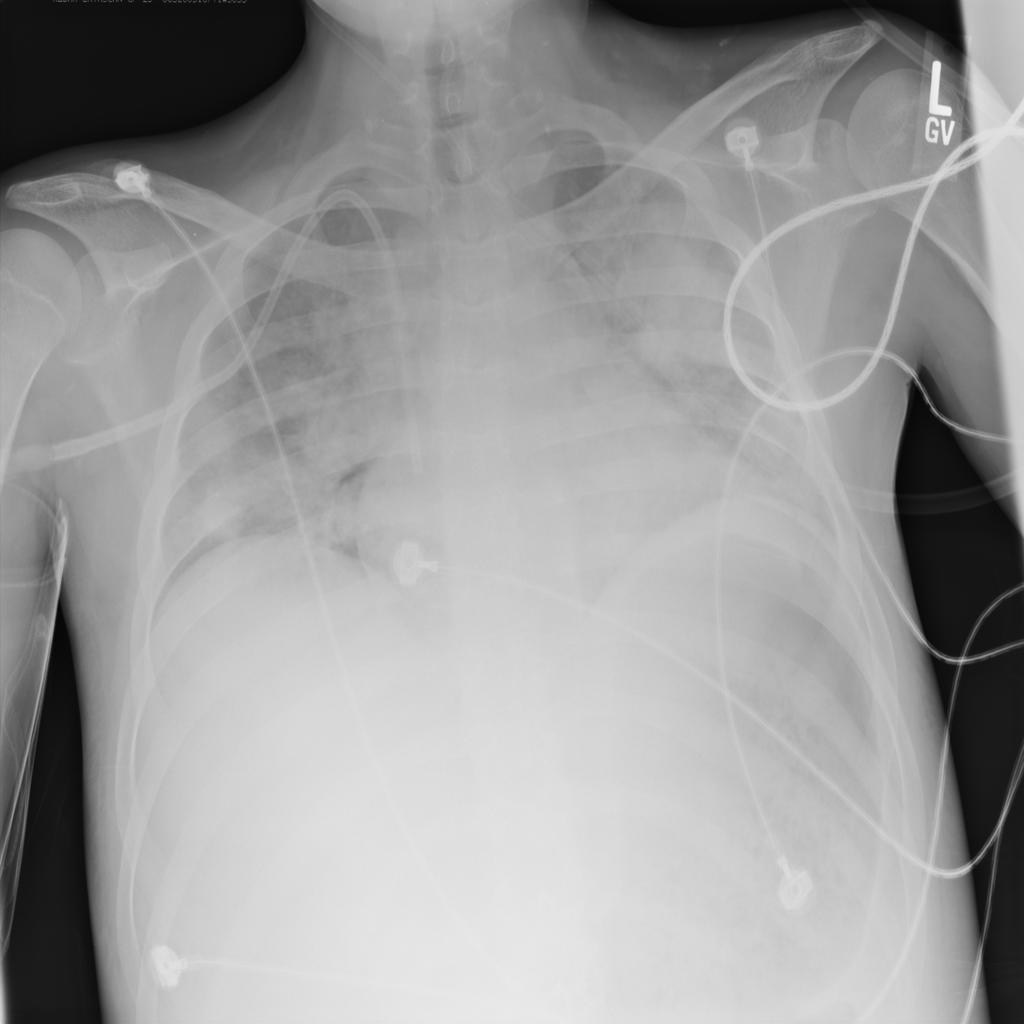

PAT-A1E2 · IMG-001Pneumonia

PAT-A1E2 · IMG-001

AP